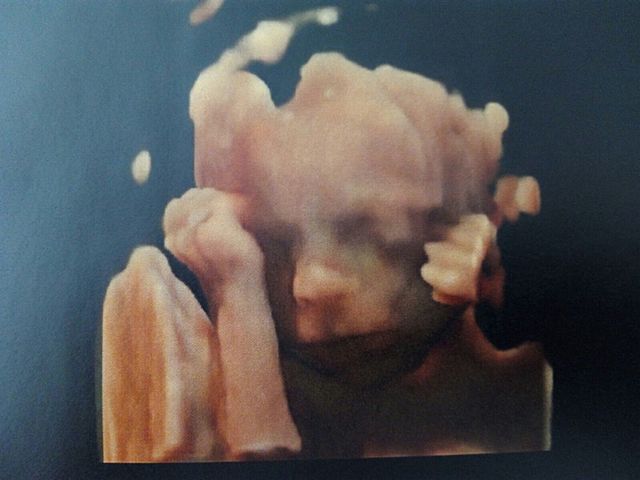

• Mi primera foto en la barriga de mi madre

Mi primera foto en la barriga de mi madre